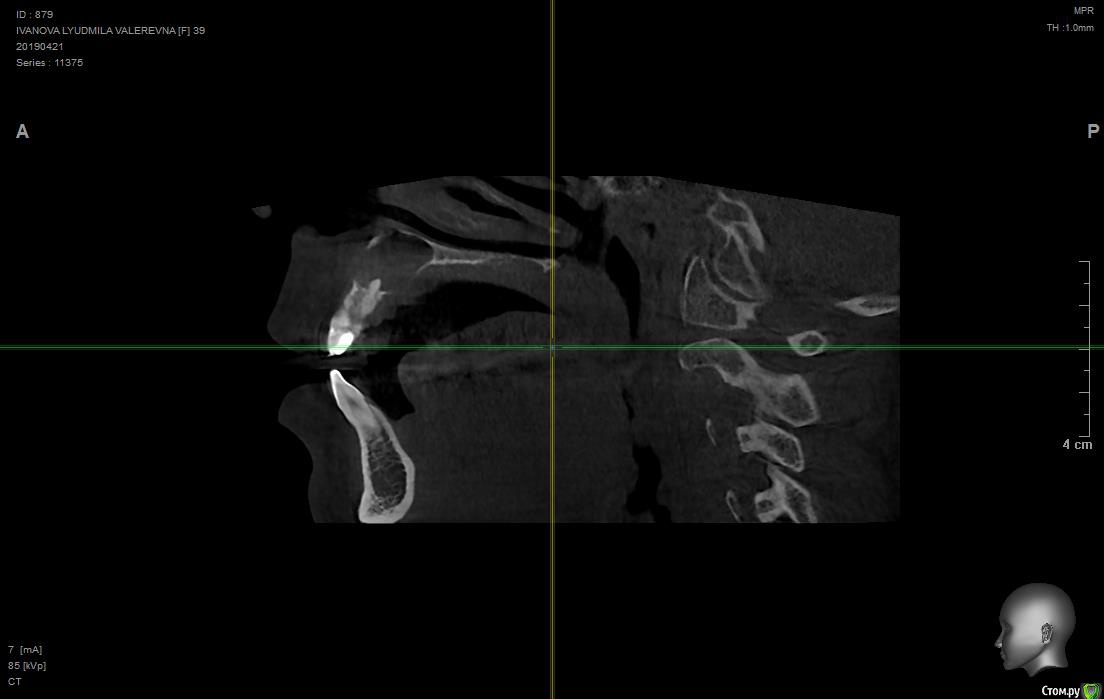

людмила10 Опубликовано 28 апреля, 2019 Поделиться Опубликовано 28 апреля, 2019 Здравствуйте доктора , помогите разобраться была у стоматолога сделали кт оказалась огромная киста на двойке уже добралась до верхней челюсти и повредила мою кость, когда то на этом зубе возникла большая киста мне сделали резекцию корня что бы спасти зуб потом через пару лет оказалось что там рецидив, правда киста была маленькая, и не болела потом появился свищ, от туда выходил гной и кровь, сейчас мой врач сказал обратится к челюстно-лицевому хирургу, что бы они сделали мне биопсию так как киста большая и операцию и все от туда убрали потом нарастили мне кость в том месте где ее нет и потом он через пару месяцев поставит мне имплант , ночь не сплю всего боюсь есть не могу аппетита нет , были ли у вас такие пациент доктора, возможно все это сделать и не сойти с ума ..https://му-fils.ru/2j8jim кодовое слово QGAYKZDHSU Ссылка на комментарий

___49___ Опубликовано 28 апреля, 2019 Поделиться Опубликовано 28 апреля, 2019 Не смог скачать КТ , срезов маловато для более объективной оценки , из того что вижу - зуб уже лучше удалять вместе с кистой , проверка соседних зубов на витальность ( живые или нет) , биопсия желательна . Ссылка на комментарий